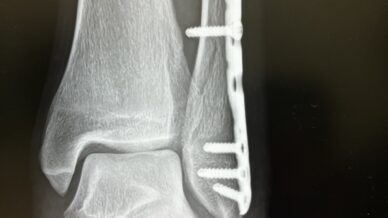

12月に骨折をした時、実は翌日に旅行を控えてました。今回、そのリベンジとして2泊の国内旅行をしてきました。場所は沖縄。万座。ANAの例のホテル。機内から撮ろうとした富士山。着陸。ジャングリア沖縄の無茶...